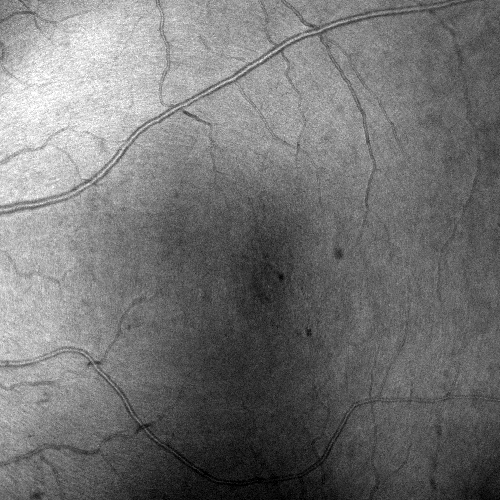

Images and estimated displacements are shown for a representative scan in Figureย 3. Tiny discontinuities prove absence of overregularization, and consistent transverse vibration indicates partial correction of ocular tremor. For quantitative analysis, we computed the median distance between the aligned A-scan displacements, and the fraction of displacements with a distance above 0.5 (problematic for supersampling) and 1 pixels (misalignments). The first and last 5% of B-scans were excluded, because they might not overlap with the orthogonal data, preventing registration. As the distributions are heavily skewed, we present box plots in Figureย 4. The three outliers in each direction in the right plot originate from the same subject, which is shown in supplementary Figureย 6. It is critical to note that the parameter density (B-scan rate 205 Hz) of the hermite splines is insufficient to fully correct ocular tremor (frequency up to 100 Hzย [16]). Therefore, this aperiodic, wave-like motion (amplitude 30โฒโฒ 1.6ย ยตm on the retinaย [16]) cannot be fully corrected, and neither is fully represented in the reproducibility error. In the transverse directions, this puts a lower accuracy limit on the evaluation scheme, but it is small compared to the pixel spacing (12ย ยตm). Using an Nvidia RTX 5000 GPU, the median and maximum runtime in the test set, excluding disk I/O which is irrelevant in clinical routine, was 8.6ย s and 31.3ย s. Tableย 1 compares average runtimes of various methods. Lastly, registration of individual B-scan repeats is demonstrated on a swept-source scanner in Figureย 5.